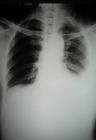

影像诊断胸腔积液量0.3~0.5L时,X线仅见肋膈角变钝;更多的积液显示有向外侧、向上的弧形上缘的积液影。平卧时积液散开,使整个肺野透亮度降低。液气胸时积液有液平面。大量积液时整个患侧阴暗,纵隔推向健侧。积液时常边缘光滑饱满,局限于叶间或肺与膈之间,超声检查有助诊断。